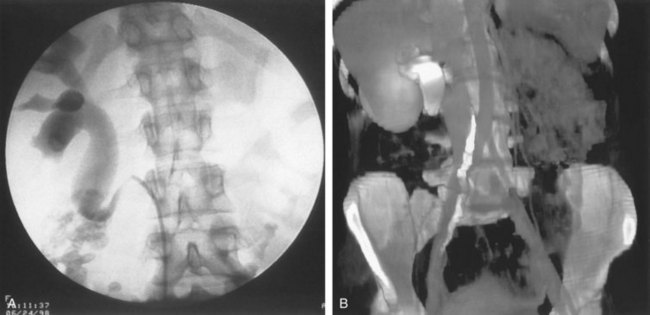

UPJ obstruction, although most often a congenital problem, can present clinically at any time of life. Historically, the most common presentation in neonates and infants was the finding of a palpable flank mass. However, the current widespread use of maternal, prenatal ultrasonography has led to a dramatic increase in the number of asymptomatic newborns being diagnosed with hydronephrosis, many of whom are subsequently found to have UPJ obstruction (Bernstein et al, 1988; Wolpert et al, 1989). A fraction of cases may also be found during evaluation of azotemia, which may result from bilateral obstruction in a functionally or anatomically solitary kidney. UPJ obstruction may also be incidentally found during studies performed to evaluate unrelated anomalies such as congenital heart disease (Roth and Gonzales, 1983). In older children or adults, intermittent abdominal or flank pain, at times associated with nausea or vomiting, is a frequent presenting symptom. Hematuria, either spontaneous or associated with otherwise relatively minor trauma, may also be an initial symptom. Laboratory findings of microhematuria, pyuria, or frank urinary tract infection might also bring an otherwise asymptomatic patient to the urologist. Rarely, hypertension may be a presenting finding (Riehle and Vaughan, 1981). Radiographic studies should be performed with a goal of determining both the anatomic site and the functional significance of an apparent obstruction. Although excretory urography remains a reasonable option for radiographic diagnosis, this study is less commonly used today. Classically, excretory urographic findings include delay in function associated with a dilated pelvicalyceal system. If the ureter is visualized, it should be of normal caliber. In some patients, symptoms may be intermittent and urography between painful episodes may be normal. In such cases the study should be repeated during an acute episode when the patient is symptomatic (Nesbit, 1956). Provocative testing with diuretic urography may allow accurate diagnosis in select cases. The patient should be well hydrated and the study then performed after injecting furosemide, 0.3 to 0.5 mg/kg (Malek, 1983) (Fig. 41–2).

Figure 41–2 A, This patient with intermittent left flank pain underwent intravenous urography. The calyces are sharp bilaterally without evidence of obstruction. However, there is a “box-shaped” pelvis on the left side, which may be associated with intermittent obstruction. B, This intravenous urogram in the same patient was performed along with injection of intravenous furosemide, which brought out the obvious left-sided ureteropelvic junction obstruction. The patient’s symptoms were subsequently relieved with a left pyeloplasty.